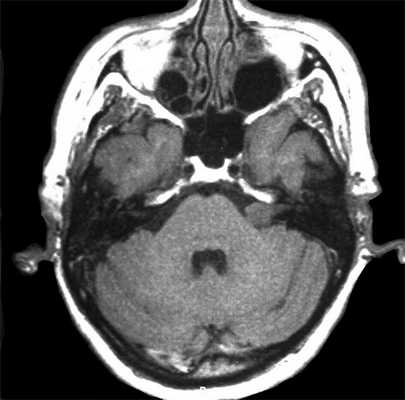

МРТ головного мозга в случае невриномы выявляет на Т1-взвешенных снимках гипо- или изоинтенсивное, а на Т2-взвешенных - гиперинтенсивное образование. Для опухолей размером 3 и более см характерна гетерогенность сигнала, связанная с наличием в них кистозных участков. Возможна визуализация деформации ствола мозга и мозжечка. При проведении контрастной МР-томографии в 70% наблюдается гетерогенное накопление контраста.

На Т2-взвешенных МРТ головного мозга невриномы имеют округлую или овальную форму, изоинтенсивны или слегка гиперинтенсивнее белого вещества, хорошо видны на фоне яркого ликвора цистерны. Крупные опухоли могут подвергаться кистозной дегенерации и включать сосуды. Мелкие невриномы имеют компонент во внутреннем слуховом проходе и как бы “утолщают“ нерв на МРТ изображениях. Как показывает опыт МРТ СПб полностью внутриканальцевые невриномы встречаются редко. МРТ в СПб при шванномах мы проводим обычно с контрастированием. Контрастирование неврином при МРТ с контрастированием хорошее, обычно однородное. Нельзя забывать, что во внутреннем слуховом проходе также может быть воспалительный процесс (неврит), приводящий к сходной клинической симптоматике. При МРТ неврит виден как отёк нерва, имеется контрастное усиление на МР томограммах.

МРТ головного мозга. Невринома слухового нерва слева с внутриканальцевым компонентом. Аксиальные Т1-зависимая МРТ, Т1-зависимая МРТ с контрастированием, и корональная Т1-зависимая МРТ с контрастированием.

Невринома слухового нерва в цистерне и внутреннем слуховом проходе. Киста (чёрная стрелка). Аксиальная Т1-взвешенная МРТ, неоднородное контрастирование.

МРТ головного мозга. Полностью внутриканальцевая невринома слухового нерва. Аксиальная Т2-зависимая МРТ, дефект на фоне СМЖ.

Нейрофиброматоз тип 2. Двухсторонние невриномы слуховых нервов (стрелки). Поперечная Т1-зависимая томограмма с контрастированием.